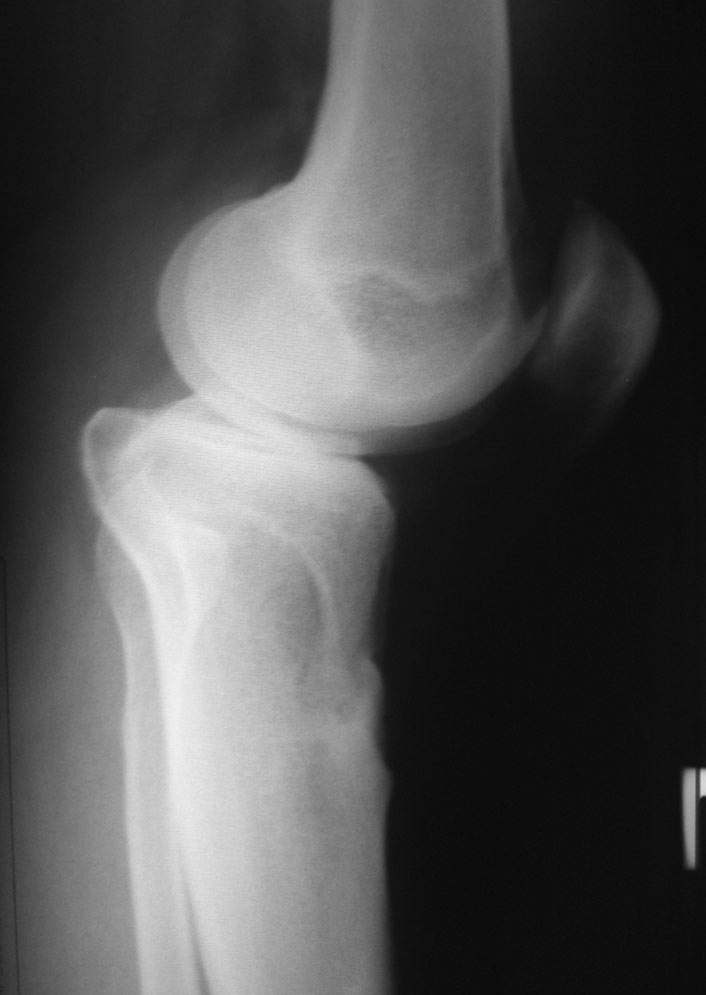

Пациент наконец то объявился вновь, и мы смогли выполнить новые снимки как лежа, так и в нагрузке.